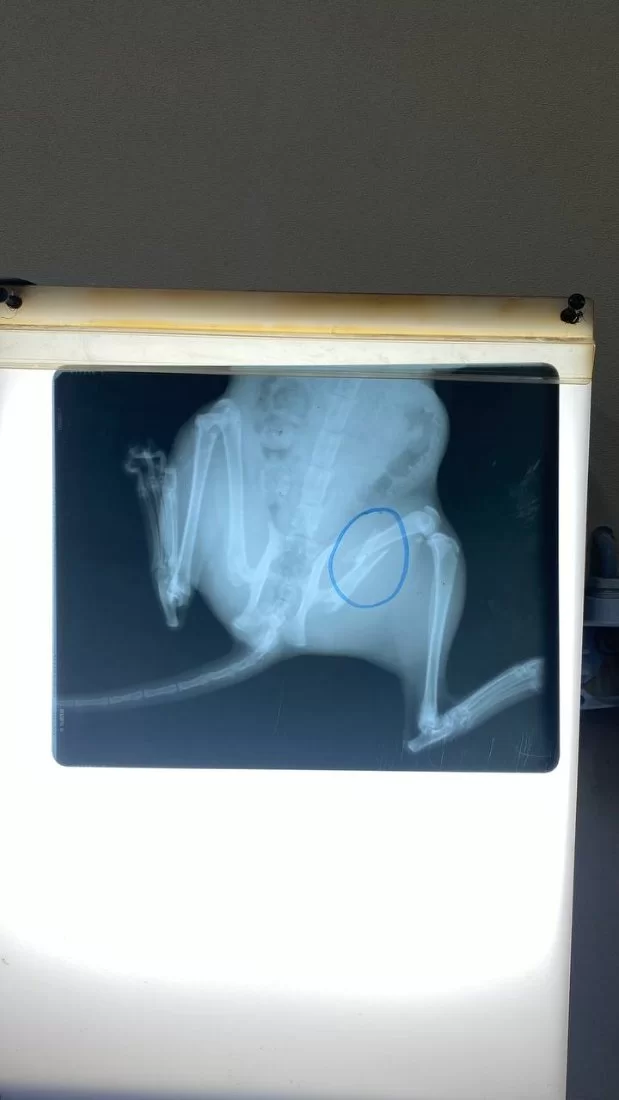

عملية تثبيت كسر مركب في كلب مالينو ( الراعي البلجيكي)

تم اليوم الموافق 21 فبراير 2024 إجراء عملية جراحية لكلب يعاني من كسر مركب في منطقة الركبة حيث قام اساتذة القسم بالتعاون مع طلبة السنه الخامسة من تثبيت الكسر بواسطه أسياخ بلاتينية وايضا تم استخراج اجسام غريبة كانت قد اخترقت الجلد اثناء تعرض الحيوان للحادث. وتاتي هذه الانشطه ضمن دور كلي